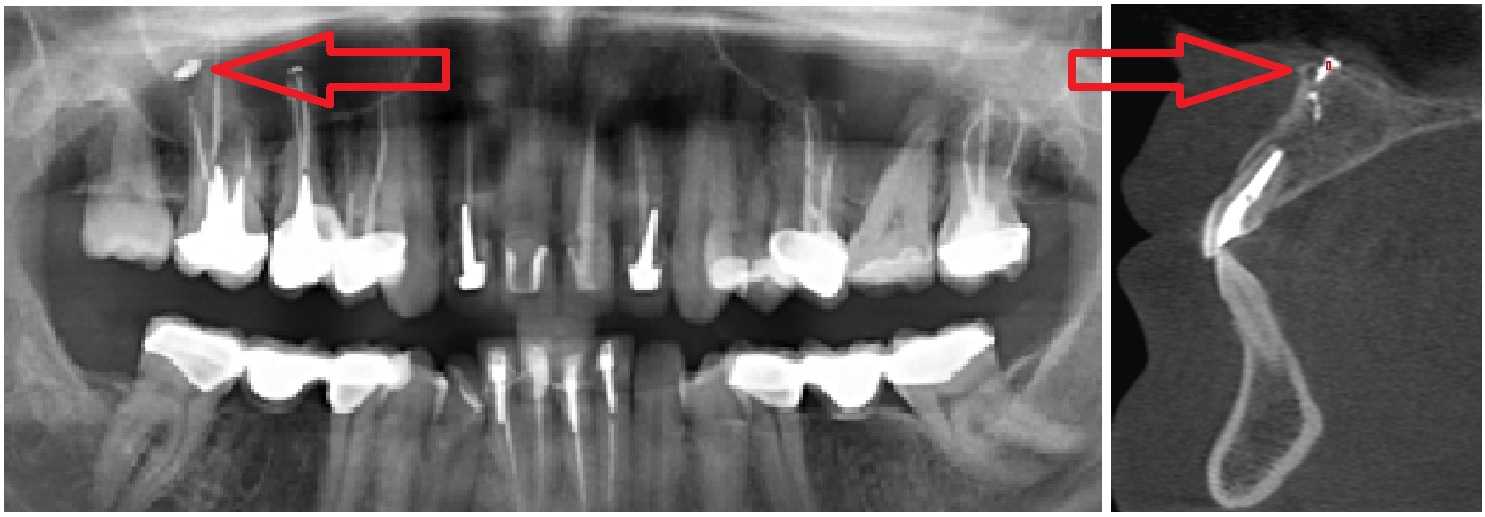

Стрелками показаны фрагменты пломбировочного материала (вид спереди и сбоку), который при пломбировании канала выпал за пределы зуба и «упёрся» в область залегания ветви тройничного нерва. У пациента долго болел зуб после лечения пульпита, затем онемела верхняя губа и часть щеки.

Вариант 2. Киста корня зуба раздражает ветвь тройничного нерва. Боль и онемение губы и щеки, боль при накусывании.

Стрелками показаны кисты корней зубов (вид спереди). Кисты в данном случае представляют собой замкнутые очаги инфекционного воспаления. Киста со временем набухает и создает давление на ветви тройничного нерва, отсюда онемение лица и боль. Осложнение после лечения пульпита.

Вариант 3. Онемение после удаления зуба. При повреждении тройничного нерва и его сплетений после удаления зуба может онеметь щека, губа, часть десны. Чем более извиты и деформированы корни зуба – тем выше риск повредить тройничный нерв при его удалении.